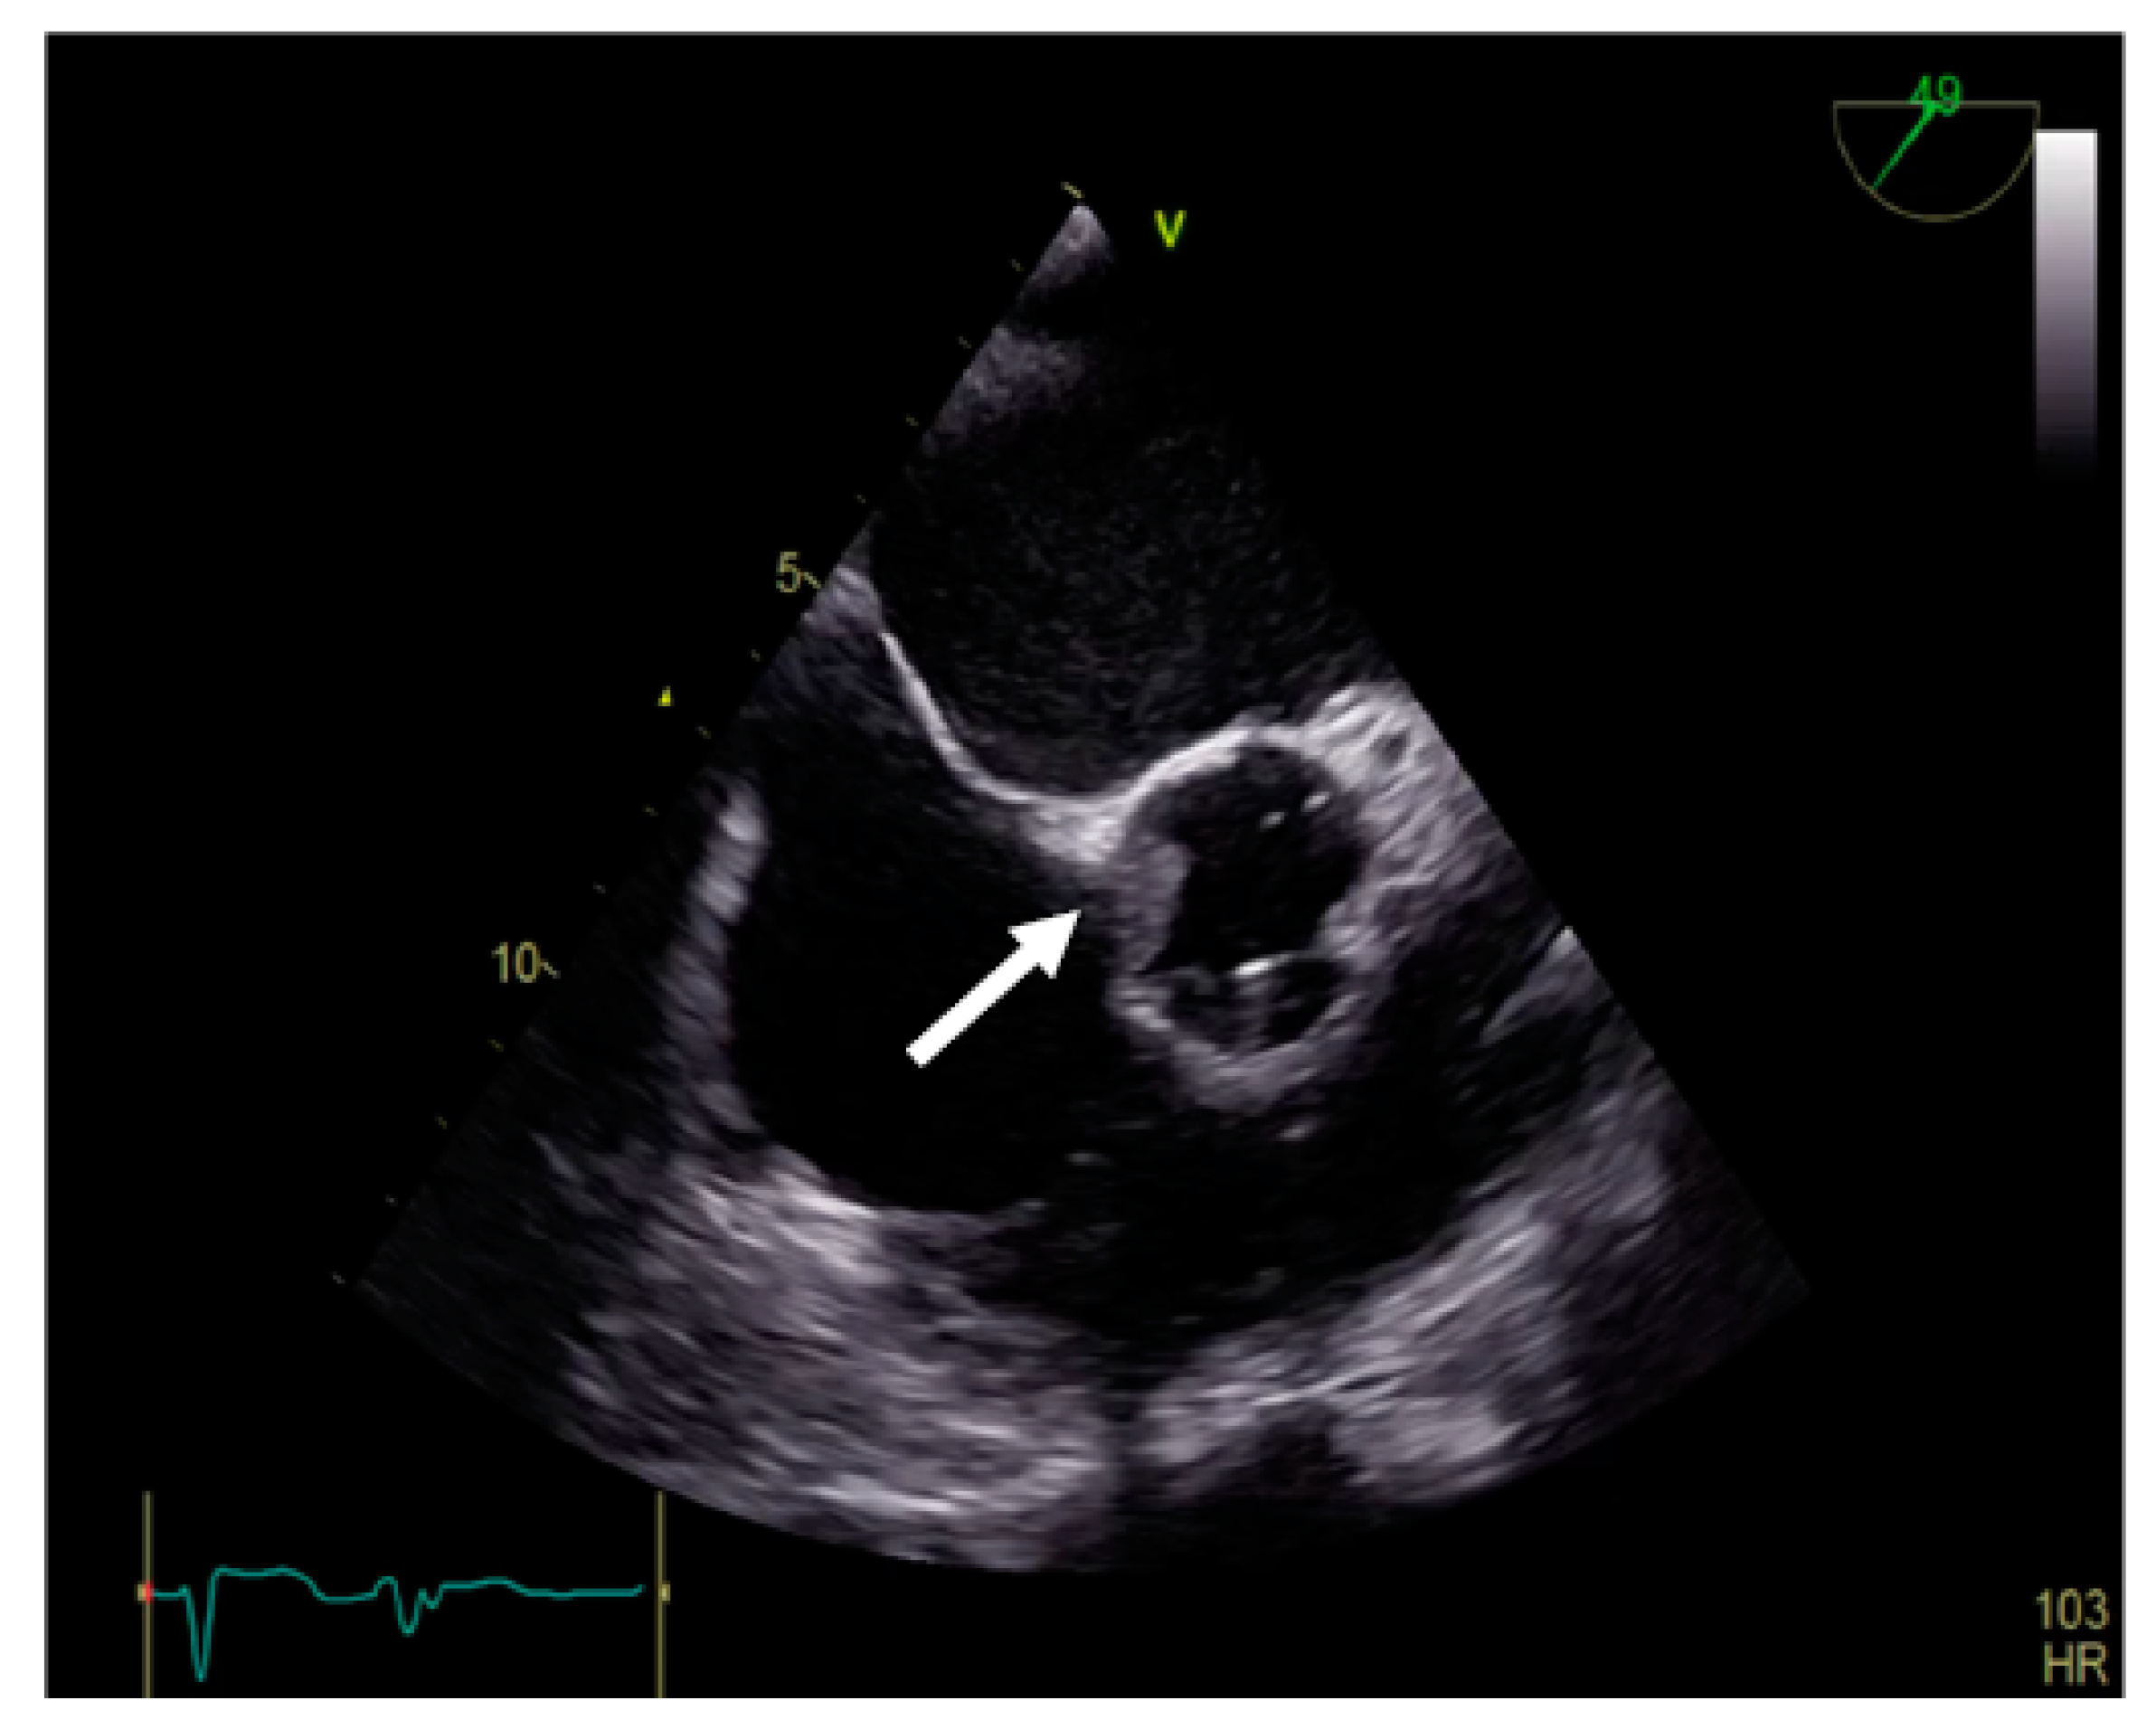

Transgastric and deep transgastric TEE views are helpful for measuring the transprosthetic gradients and LVOT diameter in order to calculate the effective area of the aortic prosthesis. Useful information is also obtained from the mid-esophageal view at 80°, where the prosthesis is visualised in a short-axis view (Figure 10). The mobility of the discs, the symmetry of their closing–opening, and the evaluation of intra- or paraprosthetic leaks are described [13]. Stress echocardiography could be beneficial in cases of uncertain diagnosis, where the assessment of the increased transprosthetic gradient is correlated with symptom reproduction. A significant increase in the gradient through the prosthesis suggests obstruction of the aortic prosthesis [13].

Figure 10.

TEE. Nonobstructive thrombus on the aortic prosthesis ring (arrow).